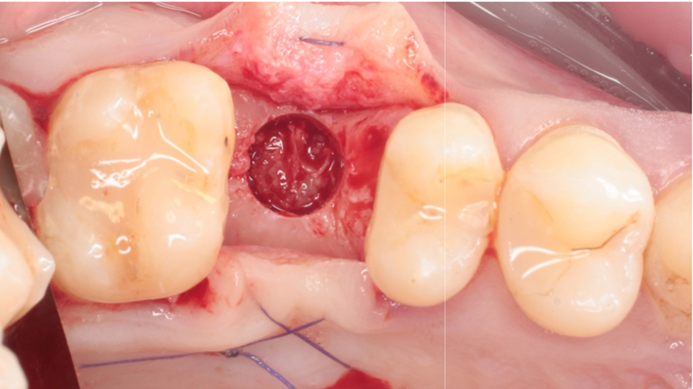

Clinical case: # 46 implant placement & GBR using i-Gen membrane for significant vertical resorption & mixed bone defect

- Courtesy of Dr. Iulian Filipov, Romania -

AnyRidge, mandibular posterior, i-Gen, resorption, bone defect, bone regeneration, space management, #46, GBR, Dr. Iulian Filipov

AnyRidge implant system, i-Gen

“AnyRidge KnifeThread achieves excellent stability in regenerated bone & even in only 3mm bone height!”